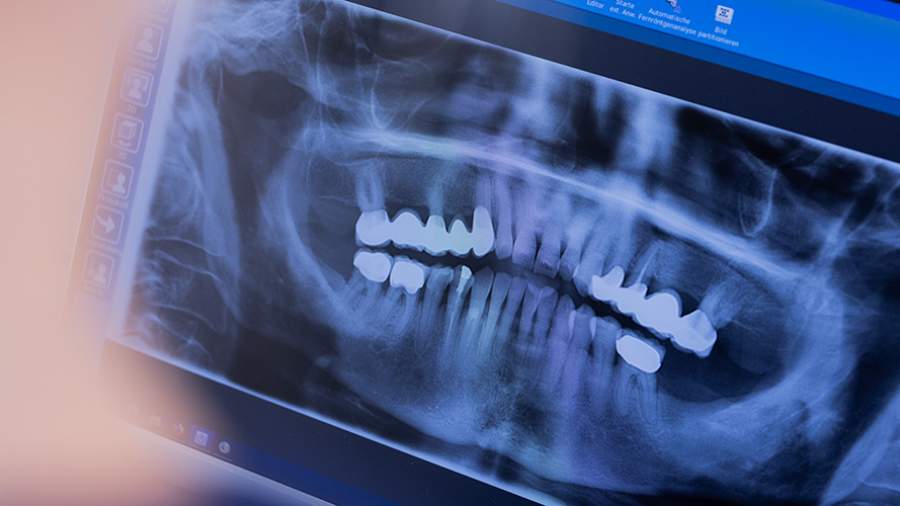

Причины разрушения зубной эмали

Специалист объяснила, что к неочевидным факторам разрушения относится привычка сочетать горячую пищу с холодными напитками. Резкие температурные скачки увеличивают чувствительность и могут стать причиной образования микротрещин на поверхности эмали. Также опасность представляют кислые продукты и напитки, такие как утренняя вода с лимоном, цитрусовые смузи или диетическая газировка, уточнила стоматолог.

Каратаева обратила внимание на важность времени чистки зубов. По ее мнению, после приема пищи кислота вызывает временную деминерализацию эмали, и механическое воздействие щетки в этот период способно ее повредить. Врач также предупредила о вреде привычки разгрызать семечки, орехи, канцелярские ручки или карандаши, поскольку это часто приводит к появлению трещин и сколов.

Эксперт добавила, что курение оказывает отрицательное воздействие как на эмаль, так и на слизистую оболочку полости рта. Кроме того, вред может нанести слишком интенсивная чистка, неправильно подобранная зубная щетка или некорректный режим использования ирригатора.

Еще одной причиной, ведущей к разрушению эмали, она назвала бруксизм — скрежетание зубами во сне. Сильное сжатие челюстей приводит к стиранию эмали и создает гипертонус в суставе.

«При гингивите или пародонтите возможно расшатывание зубов. Стресс тоже играет роль: слюна меняет защитные свойства, появляется сухость во рту, и кариес с осложнениями развивается быстрее, поэтому важно следить за эмоциональным состоянием и пить больше воды», — рекомендовала эксперт в разговоре с Lenta.Ru.